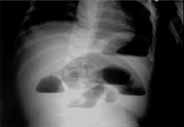

Un paciente de 5 meses de edad se presentó con cuadro clínico de tres días de evolución de vómito, inicialmente alimentario, que luego se tornó bilioso, asociado a ausencia de deposición. En el examen físico se apreció un abdomen blando con peristaltismo presente, pero disminuido, y sin masas palpables. La radiografía simple de abdomen mostró dilatación de asas delgadas y presencia de niveles hidroaéreos, hallazgos sugestivos de obstrucción intestinal mecánica (Figura 1). La ecografía abdominal fue reportada como sugestiva de obstrucción intestinal sin que se apreciaran masas. Con este diagnóstico de obstrucción intestinal mecánica se decidió practicar una laparotomía exploratoria en la que se encontró un quiste de 5 cm de diámetro, con contenido quiloso, localizado a 10 cm de la unión duodeno yeyunal, que causaba compresión del asa intestinal (Figura 2). Se practicó seguidamente una resección intestinal y una anastomosis termino-terminal. El informe de patología mostró una dilatación marcada de vasos linfáticos y quistes que comprometían desde la submucosa hasta el mesenterio, con contenido proteináceo y presencia de histiocitos espumosos, hallazgos compatibles con un quiste quiloso (Figura 3). La evolución del paciente en el postoperatorio fue satisfactoria.

Figura 1. Radiografía de abdomen con niveles hidroaéreos

El diagnóstico clínico usualmente se confirma con una radiografía simple del abdomen y una ecografía abdominal. La primera suele mostrar niveles hidroaéreos si hay obstrucción intestinal5-8, mientras que la ecografía evidencia el signo del nivel “líquido-líquido”, que puede ser sugestivo del quiste de quilo; sin embargo, el diagnóstico definitivo es intraoperatorio3.